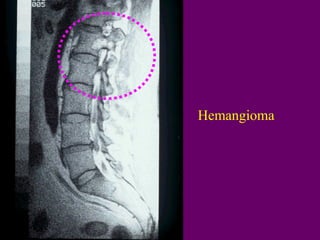

Hemangioma

Thoaùi hoaù môõ ><Hemangioma